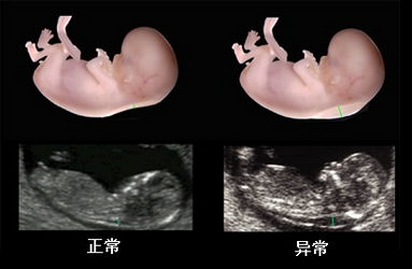

1.四维彩超:由于四维彩超是一种立体B超检查,所以除了能检查常规的项目之外,还可针对心肝脾肺各个脏器 及唇腭裂方面的筛查。

2.四维彩超:四维彩超在怀孕20——28周内做为宜。在怀孕20周后,胎儿大脑便开始迅速发育,肢体发育也已经基本完成,加上胎儿的大小和羊水比较适中,骨骼回声影响比较小,成像会比较清晰。

对胎儿全面排畸,孕妈妈除了需要做系统彩超以外,还需要做四维彩超。因为,系统彩超仅仅是对胎儿先天愚型和智力缺陷等进行排查。四维彩超是对胎儿面部、颜色等体表器官进行筛查。因此,贵阳妇产医院产科医生建议,全面排畸系统彩超和四维彩超都要做。